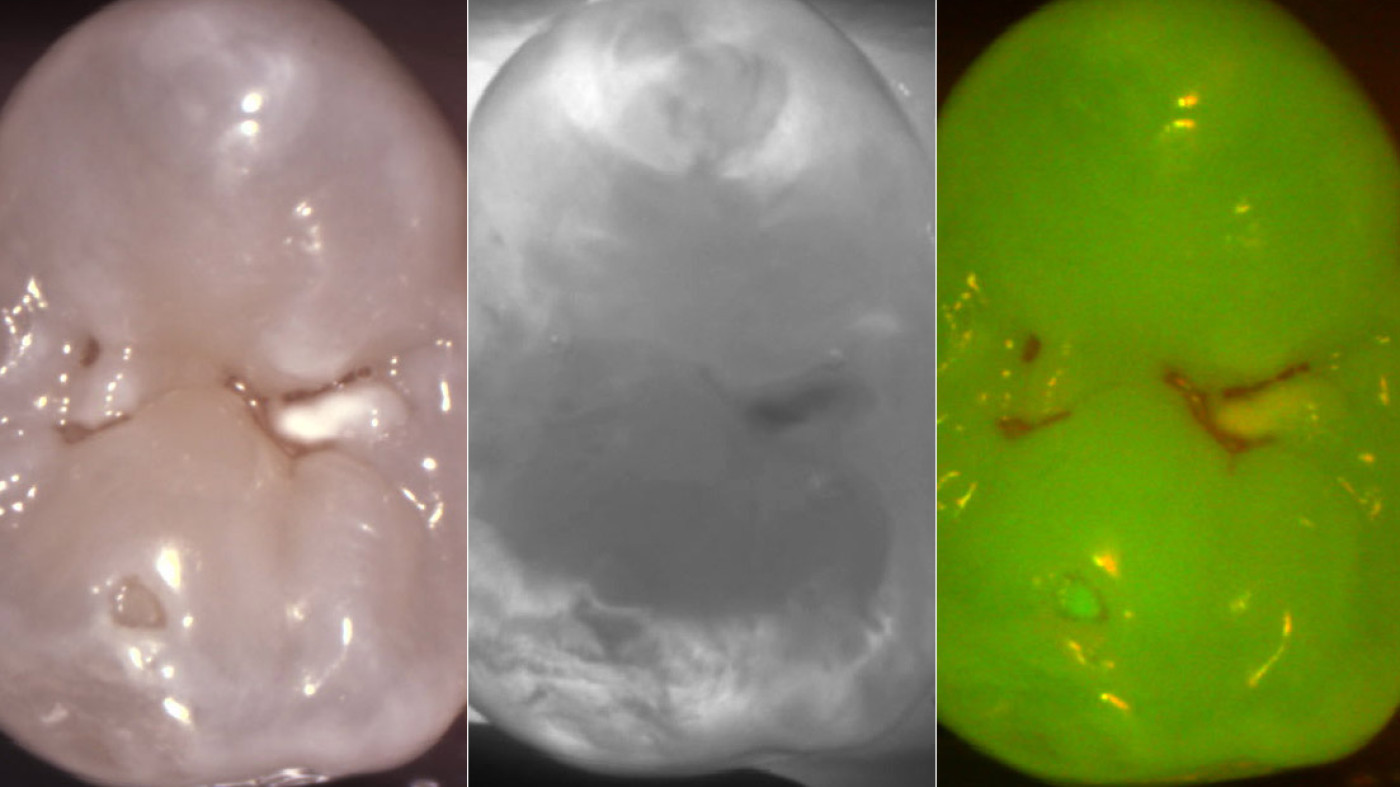

KaVo Introduces the Revolutionary DIAGNOcam Vision Full HD: Triple Diagnostics Simultaneously.

The DIAGNOcam Vision Full HD leverages cutting-edge transillumination and fluorescence technology to deliver immediate, radiation-free diagnostic images.

• Transillumination: Light waves illuminate the tooth, creating X-ray-like images for early detection of occlusal, interproximal, and secondary caries, as well as cracks and fractures, with extreme accuracy.

• Fluorescence: Detection of bacteria on occlusal surfaces, confirmation that all caries have been removed, and a final check before placing restorations or sealants.

• Intraoral Camera: Permanent auto-focus for crystal clear images both intra- and extra-orally, a gyro sensor for easy orientation, and distortion-free macro photos to detect the smallest lesions or cracks in filling materials.

KaVo DIAGNOcam Vision Full HD offers three diagnostic recordings in full HD resolution with just one click.

• 1-Click Images: Transillumination, fluorescence and intra-oral modes available with just a single click